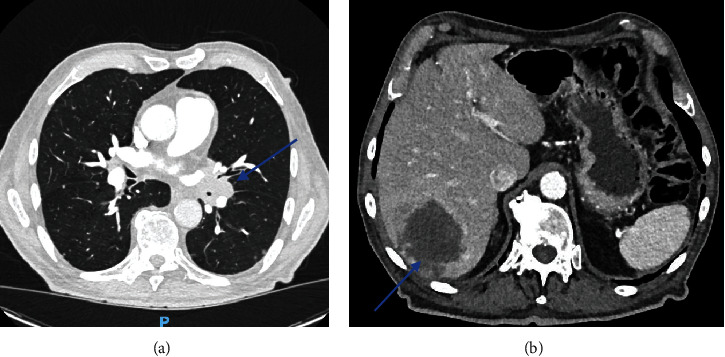

Background: The penis is a relatively uncommon organ for metastases. Secondary lesions often originate from the bladder, prostate, or rectosigmoid cancers. Only a few cases have described penile lesions secondary to lung cancers, mostly as a later complication. Case Description: We hereby report the case of an 86-year-old male patient who presented with a 3-week-long nonpainful priapism. A penile Doppler ultrasound and a chest and abdominal CT scan were performed, showing a left hilar lung mass as well as lesions in the liver, the adrenal glands, the pancreas, bone structures, and the penis. Penile metastasis is associated with a poor prognosis because of the frequent disseminated malignant lesions in other sites. Conclusion: Malignant priapism should be suspected, especially in patients with no evident risk factors for priapism (hematological diseases, drugs, alcohol, neurological diseases, or metabolic disorders).